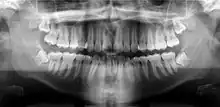

Un orthopantomogramme, abrégé par les sigles OPT ou OPG, est une radiographie panoramique de toute la denture. À ce titre, cet examen est plus souvent appelé « panoramique dentaire ».

Il consiste en une mise à plat de l'arc dentaire, d'une oreille à une autre.

Radiographie panoramique dentaire

Le cliché panoramique donne une vue d’ensemble des arcades dentaires, des maxillaires, des articulations et des sinus. Il est utilisé pour diagnostiquer un grand nombre de conditions pathologiques : infections, fractures des mâchoires, kystes et granulomes à la racine des dents, et certaines affections osseuses (maladie de Paget)…

On effectue aussi un panoramique dentaire pour évaluer la distribution des dents, la perte osseuse et les parodontites, ou encore pour visualiser l’ensemble des germes de dents chez l’enfant, pour définir son âge dentaire. Par ailleurs, il s’avère également utile pour décider du bien-fondé de la pose d’implants ou de la localisation des racines artificielles avant leur pose.